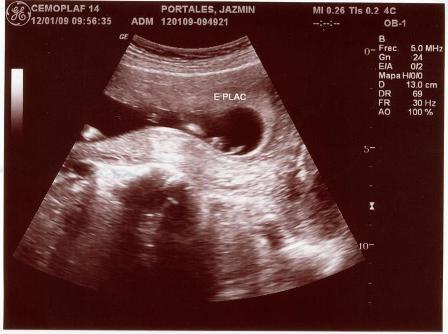

Fotos del 19 En 2009:

Informe:

Embarazo con feto de 13 semanas 4 días +/- 1 semana.

LCF: 151 lpm

Fémur: 1

Estática fetal: Variable

Movimientos: Activos normales

Placenta: Anterior lateral izquierda grado 0

Líquido Anmiótico: Cantidad normal

Impresión: Feto único, vivo con movimientos normales y actividad cardiaca normal. OCI cerrado.

Ovarios normales y fondo de saco de Douglas libre.